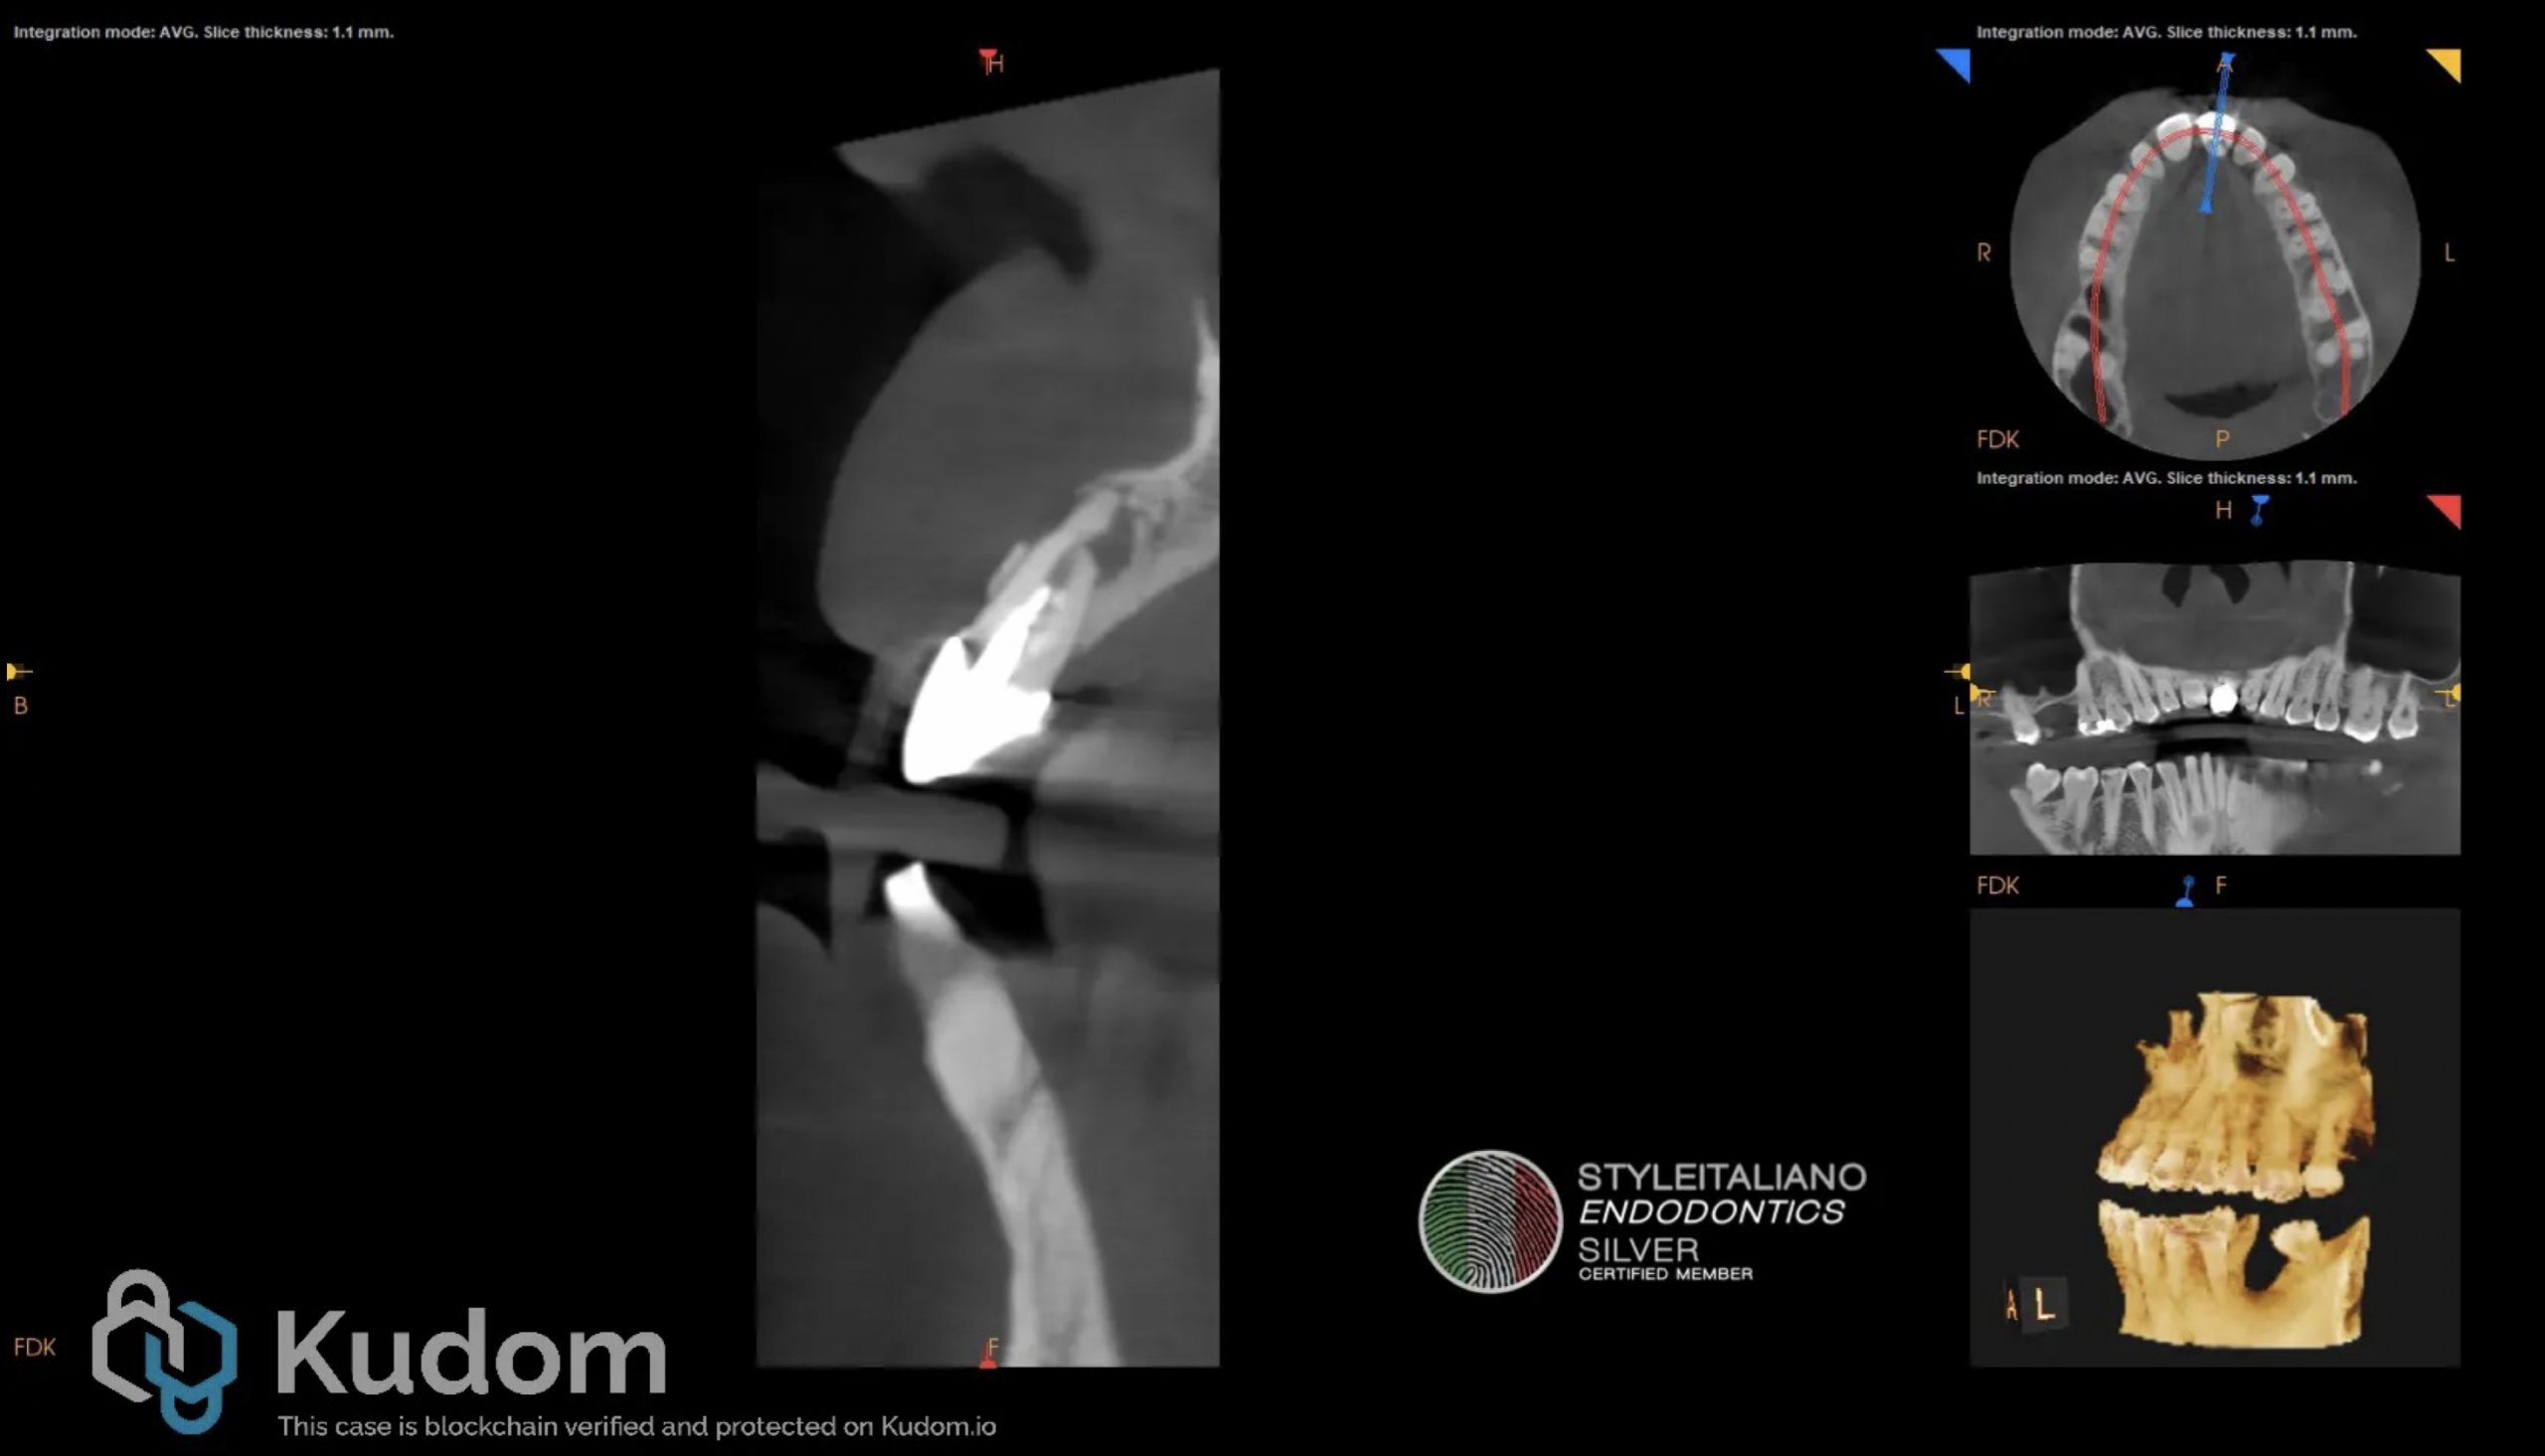

Fig. 4

Post endodontic treatment status of tooth 2.1 CB-CT view.